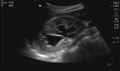

Normal

Abnormal